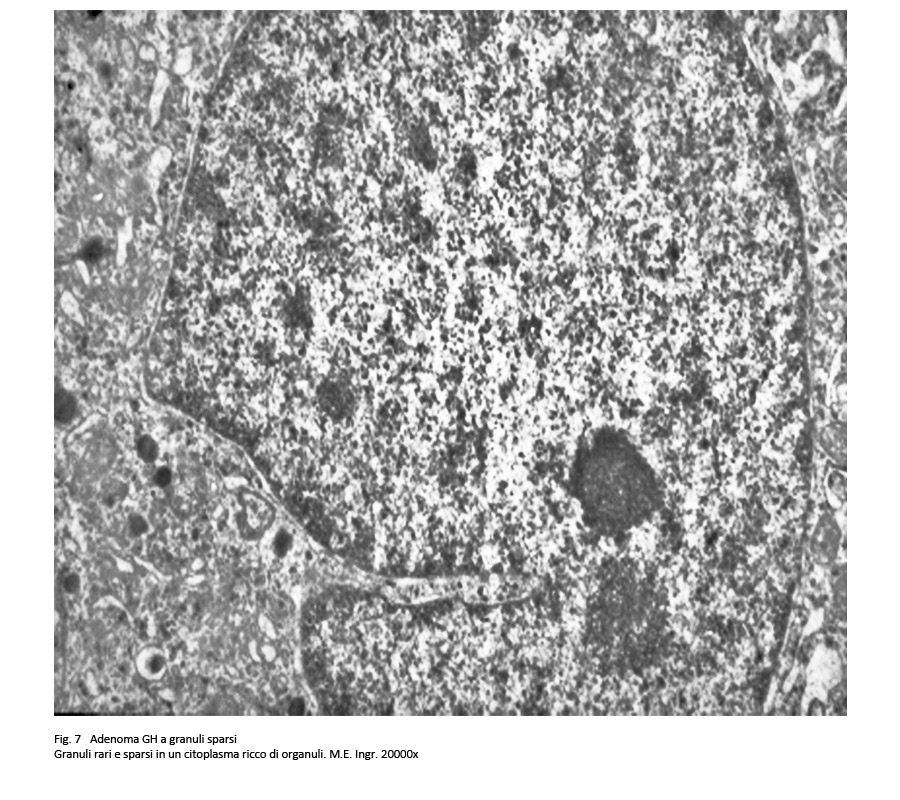

Adenoma a granuli sparsi secernente GH

L’architettura microscopica di questo adenoma ripete quella del sottotipo precedentemente descritto. Le cellule sono di piccola – media taglia e hanno un citoplasma lievemente acidofilo o cromofobo.

I nuclei sono rotondeggianti o frequentemente pleomorfi, sono ipercromatinici e sono forniti di un preminente nucleolo; in sede paranucleare si possono repertare aree chiare e “corpi fibrosi”.

fig.7

Al microscopio elettronico si rivelano nel citoplasma quote cospicue di ergastoplasma rugoso con una disposizione a forma di strutture convolute; a queste si associano granuli di secrezione di piccola taglia, 100-250 nm, distribuiti in modo sparso e la presenza di aggregati addensati di filamenti intermedi e di reticolo endoplasmico, quale espressione ultrastrutturale dei “corpi fibrosi”.

Le ricerche di immunoistochimica hanno evidenziato una ridotta immunoespressività per l’ormone GH, e un indice di attività proliferativa, ricavato attraverso la espressività al MIB-1, vicino allo zero; queste indagini hanno esplicitato una positività immunologica per la citocheratina a basso peso molecolare e in particolare per la citocheratina.

Le modalità di crescita sono frequentemente infiltranti e possono colpire le strutture anatomiche circostanti.